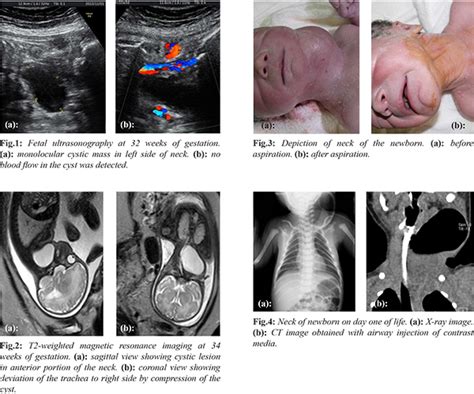

Pyriform Sinus Fistula Presenting as Fetal Cervical Cyst

casereports.in